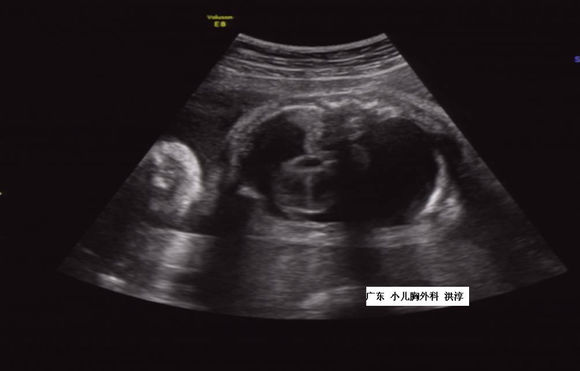

1.产前超声:产前诊断FHT主要依靠超声检查,超声表现为胎儿胸腔内心肺之间片状无回声区。单侧大量胸腔积液可有占位效应,出现心脏及纵膈移位,肺脏常被压缩变小。继发于胎儿水肿的胸腔积液,多为双侧性,双侧胸腔积液时表现为“蝙蝠翅膀”声像图。